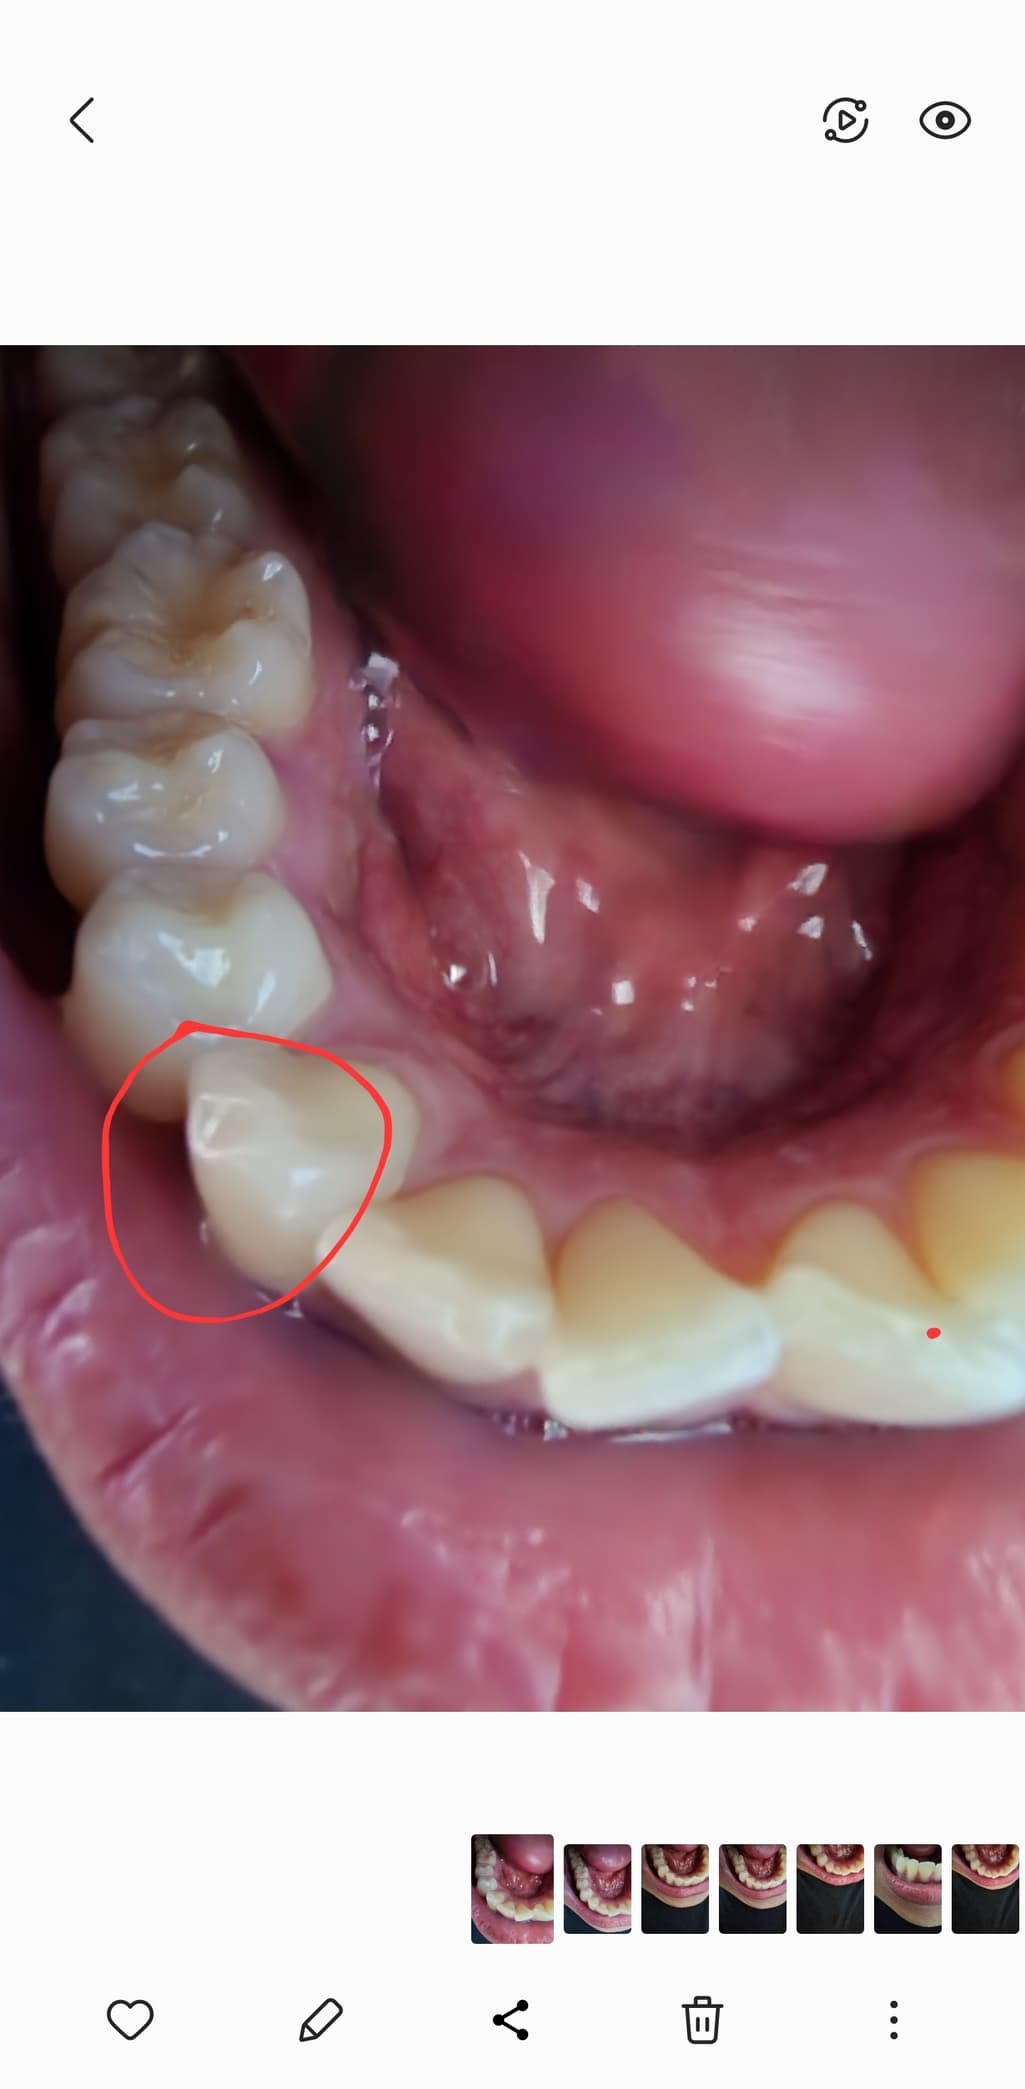

깨진 이 그대로 두면 닳으나요?

쇠젓가락을 씹어서 이가 깨졌는데요

오늘 치과를 가서 검사를 받으니 스크래치난 부분도 없고

깨진 부분은 딱히 이상 없다고 그냥 써도 된다는데

• 1번 째 사진